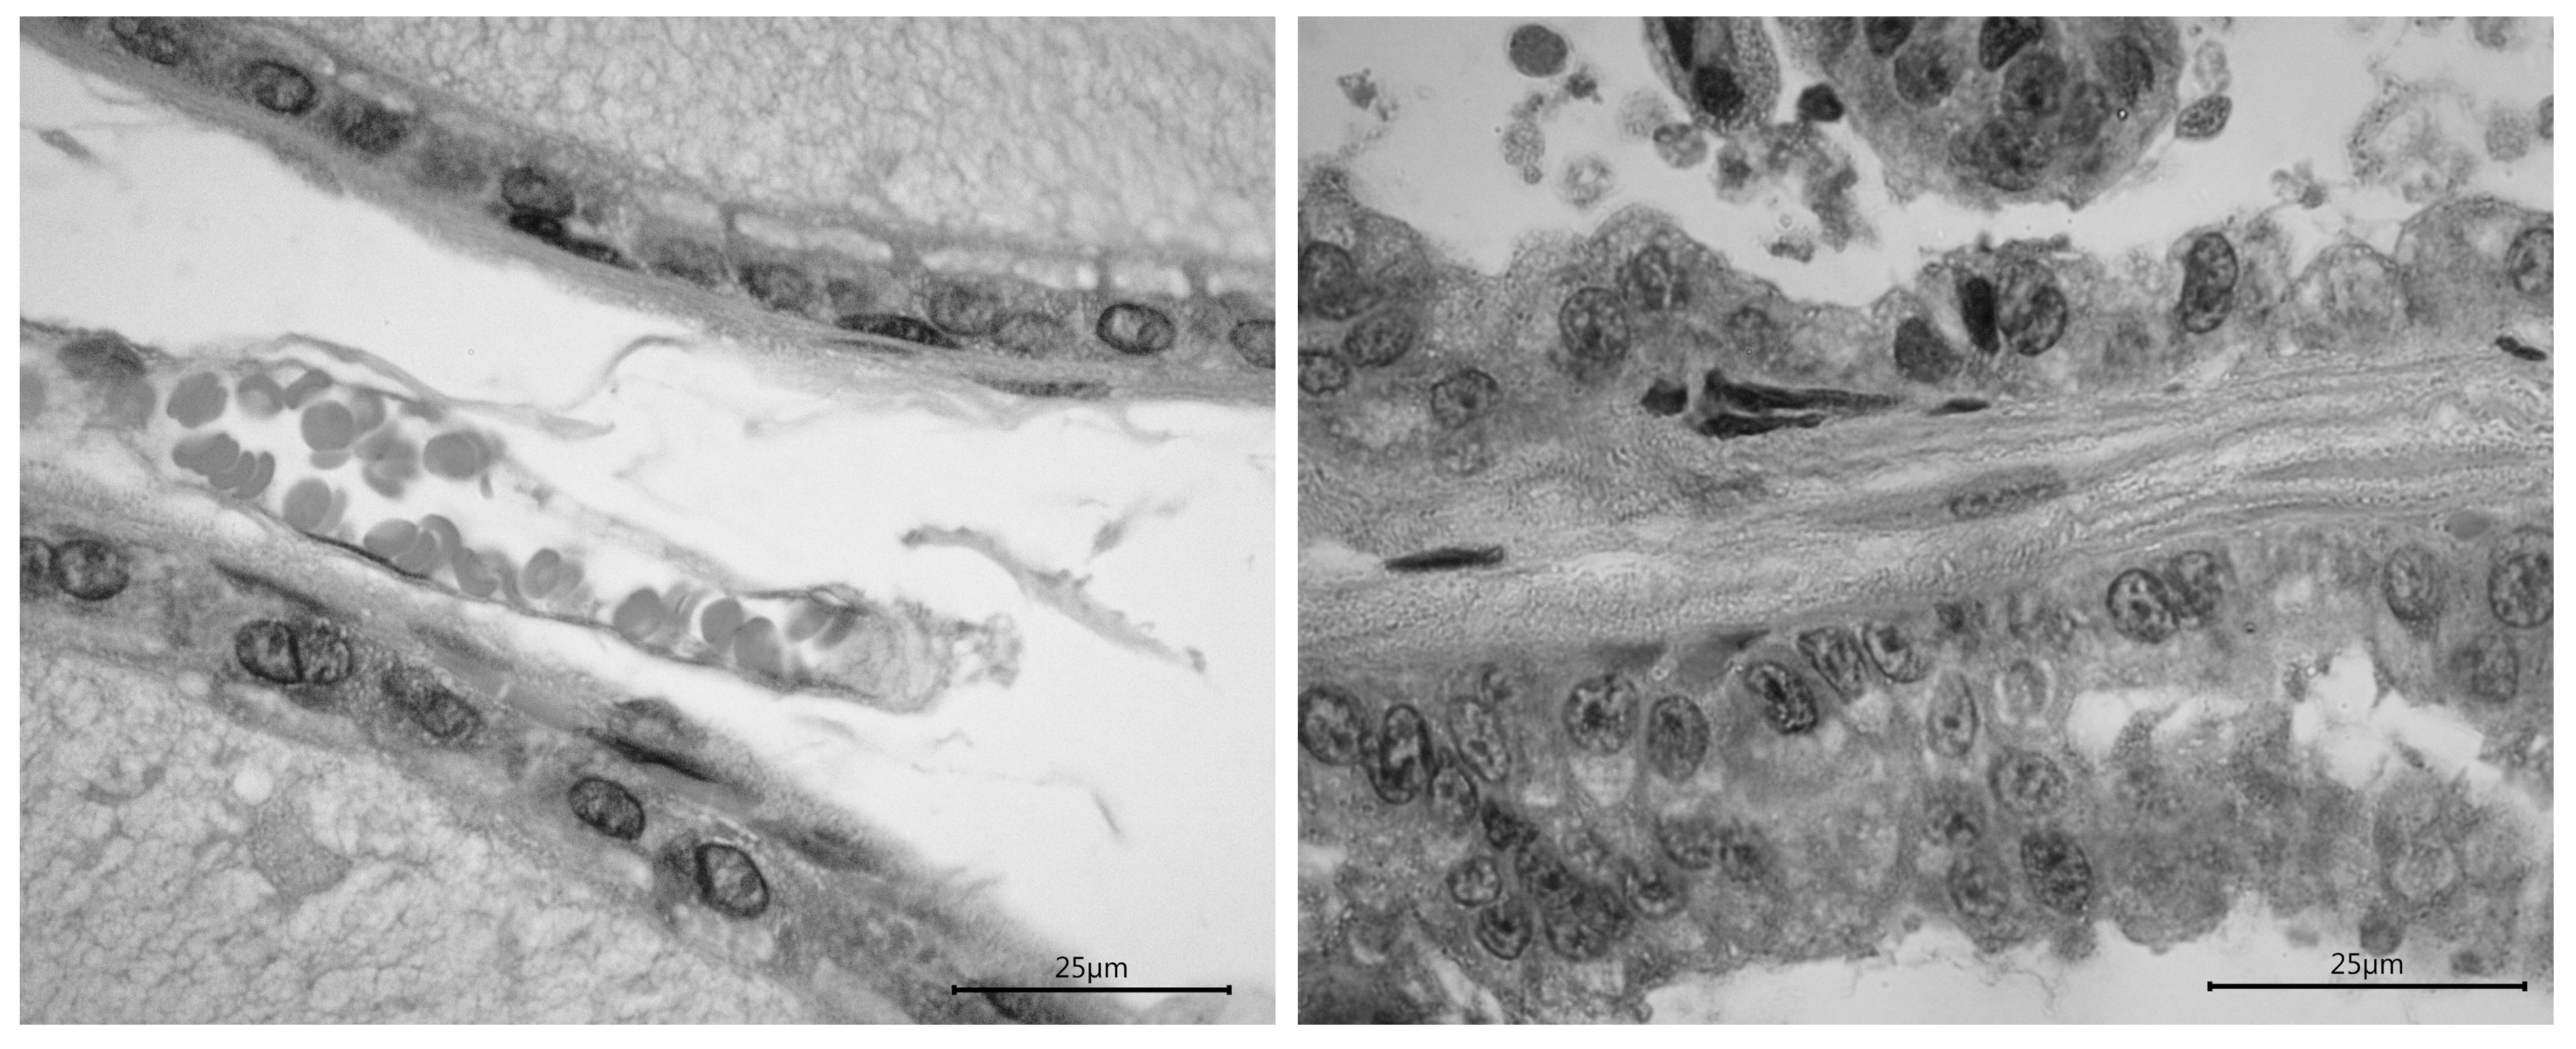

The histological analysis showed that the dorsolateral prostate had a cubic epithelium in each control male, while 3 out of 5 autistic males had an abnormal size or anisocytosis. The image analysis also revealed an even interstitial space with collagen in every control male, but in 2 out of 5 autistic males the space was compressed and showed mononuclear cells; the nuclei had an homogeneous size with a polarity basal location in control males, but in every autistic male the polarity was lost and in two males nuclei showed an abnormal size or anisokaryosis. The ventrolateral prostate showed similar alterations(Fig. 4).

Figure 4. Representative images of the dorsolateral prostate in a control male (left photo) and an autistic male (right photo). The images reveal the differences between groups; it is remarkable the alteration in the epithelium and nuclei. Calibration bars = 25 µm.

In addition to behavior, the histology of the autistic prostate showed cellular cytoarchitecture conditions, such as dysplasia and anisokaryosis, that are consistent with cancerous tissue.41 Previously we reported similar cellular changes in the prostate induced by testosterone treatment.42 We have also shown that the execution of sexual behavior produces an increase in both serum levels of testosterone and androgen receptors in the prostate.43 Furthermore, we also showed that similar effects at the prostate are produced after lesions of the autonomic nerves that supply the gland.44 All these data strongly suggest that the prostate is an autism-sensitive gland for the development of cancer and its alteration could add to the behavioral tendency for infertility. Although a number of studies have reported correlations between autism and cancer,45-47 to our knowledge, this is the first study indicating a high risk for the development of prostate cancer in autistic males. Therefore, as far as new information become available, the analysis of prostate health in sexually mature men with autism should be an area of particular scrutiny.